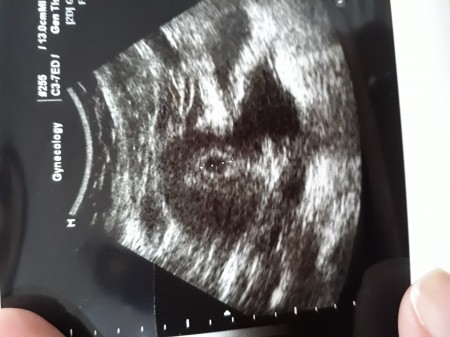

Yolk Sac Var Bebek Gorunmuyor Hamilelik Donemi Genel

Kese Var Bebek Yok Hamilelik Donemi Genel

6 3 Hamileyim Kese Var Bebek Yok Kadinlar Kulubu